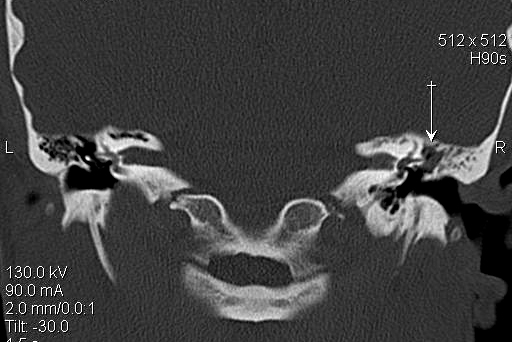

JFC Aticitis colesteatomatosa.